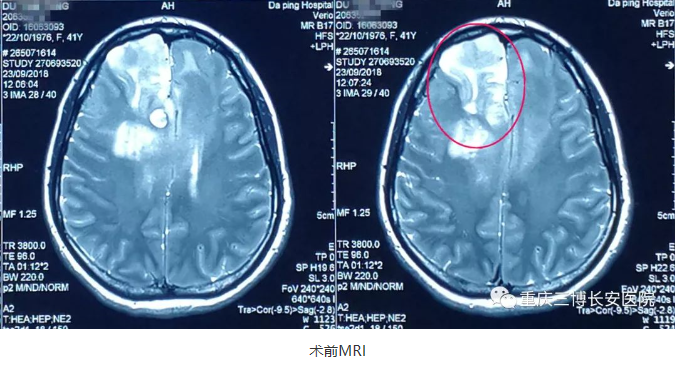

杜某今年41岁,本想趁这个国庆节陪家人、陪孩子出去好好玩一玩,可是正怀着期待的心情等待假期到来时,节前一周突然无明显诱因出现头痛,没有出现其他不适。老是头痛也不是个事,为了能够在假期更好的游玩,杜某遂前往市里某三甲医院就诊,外院MRI检查提示:双侧额叶多发异常信号并累及胼胝体膝部、体部,考虑高级别胶质瘤(WHOⅢ级)可能性大。脑部有肿瘤?怎么办?在经过多方打听和网络搜索后得知重庆三博长安医院脑科实力雄厚,共享北京三博脑科专家资源,遂前来就诊。

杨某今年40岁,是一位光荣的人民教师,并且是一位班主任,平时工作压力较大,1月前无明显诱因出现头痛,因才开学,工作繁忙,没有太在意,可是随着时间推移,疼痛呈渐进性加重,并伴头昏,恶心。脑部出了问题?不能在拖了,身体要紧。经朋友介绍重庆三博长安医院脑科实力雄厚,共享北京三博脑科专家资源,遂前来就诊,MRI提示:多发性胶质瘤。

术前,吴斌教授与患者家属进行沟通,详细说明手术面临的各种情况及围手术期治疗方案。

术前,吴斌教授与患者家属进行沟通,详细介绍手术方案、说明手术面临的各种情况及围手术期治疗方案。